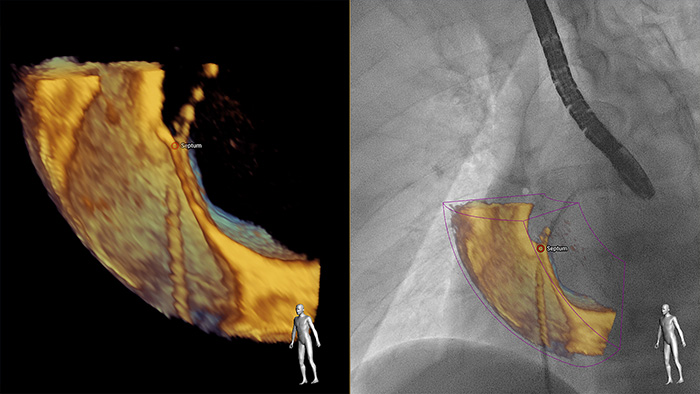

EchoNavigator fusionne automatiquement l'ETO 3D et la radiographie en temps réel pour vous permettre de guider intuitivement votre appareil dans l'espace 3D plus rapidement.